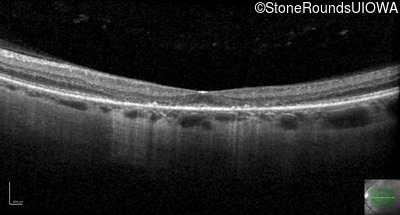

Age at visit: 40 years

OD OS

This 40 year old woman first noticed a reduction of her visual acuity about two years ago. She has been sensitive to light for as long as she can remember.

Diagnosis & molecular findings

Disease Gene Allele 1 variant(s) Allele 2 variant(s) Inheritance mode

AD Stargardt Disease PROM1 Arg373Cys CGC>TGC   AD